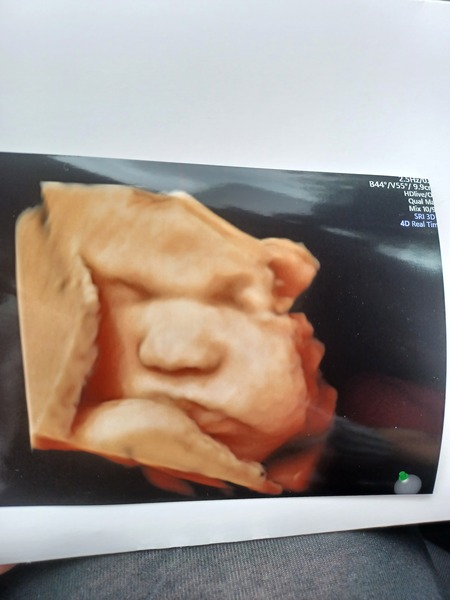

We have a perfect baby ❤️ measuring ahead again! So now due 26th February! Measuring 12 weeks +3 days.

NT measured 1.3mm which is really good!

No sign of baby yet! Had a private scan today and she is fine. I've got my growth scan at the hospital on Monday so will know more then. Picture attached!

Wow @HalGem99 lovely to see that little face!

@HalGem99 what a beautiful baby you have there 😍